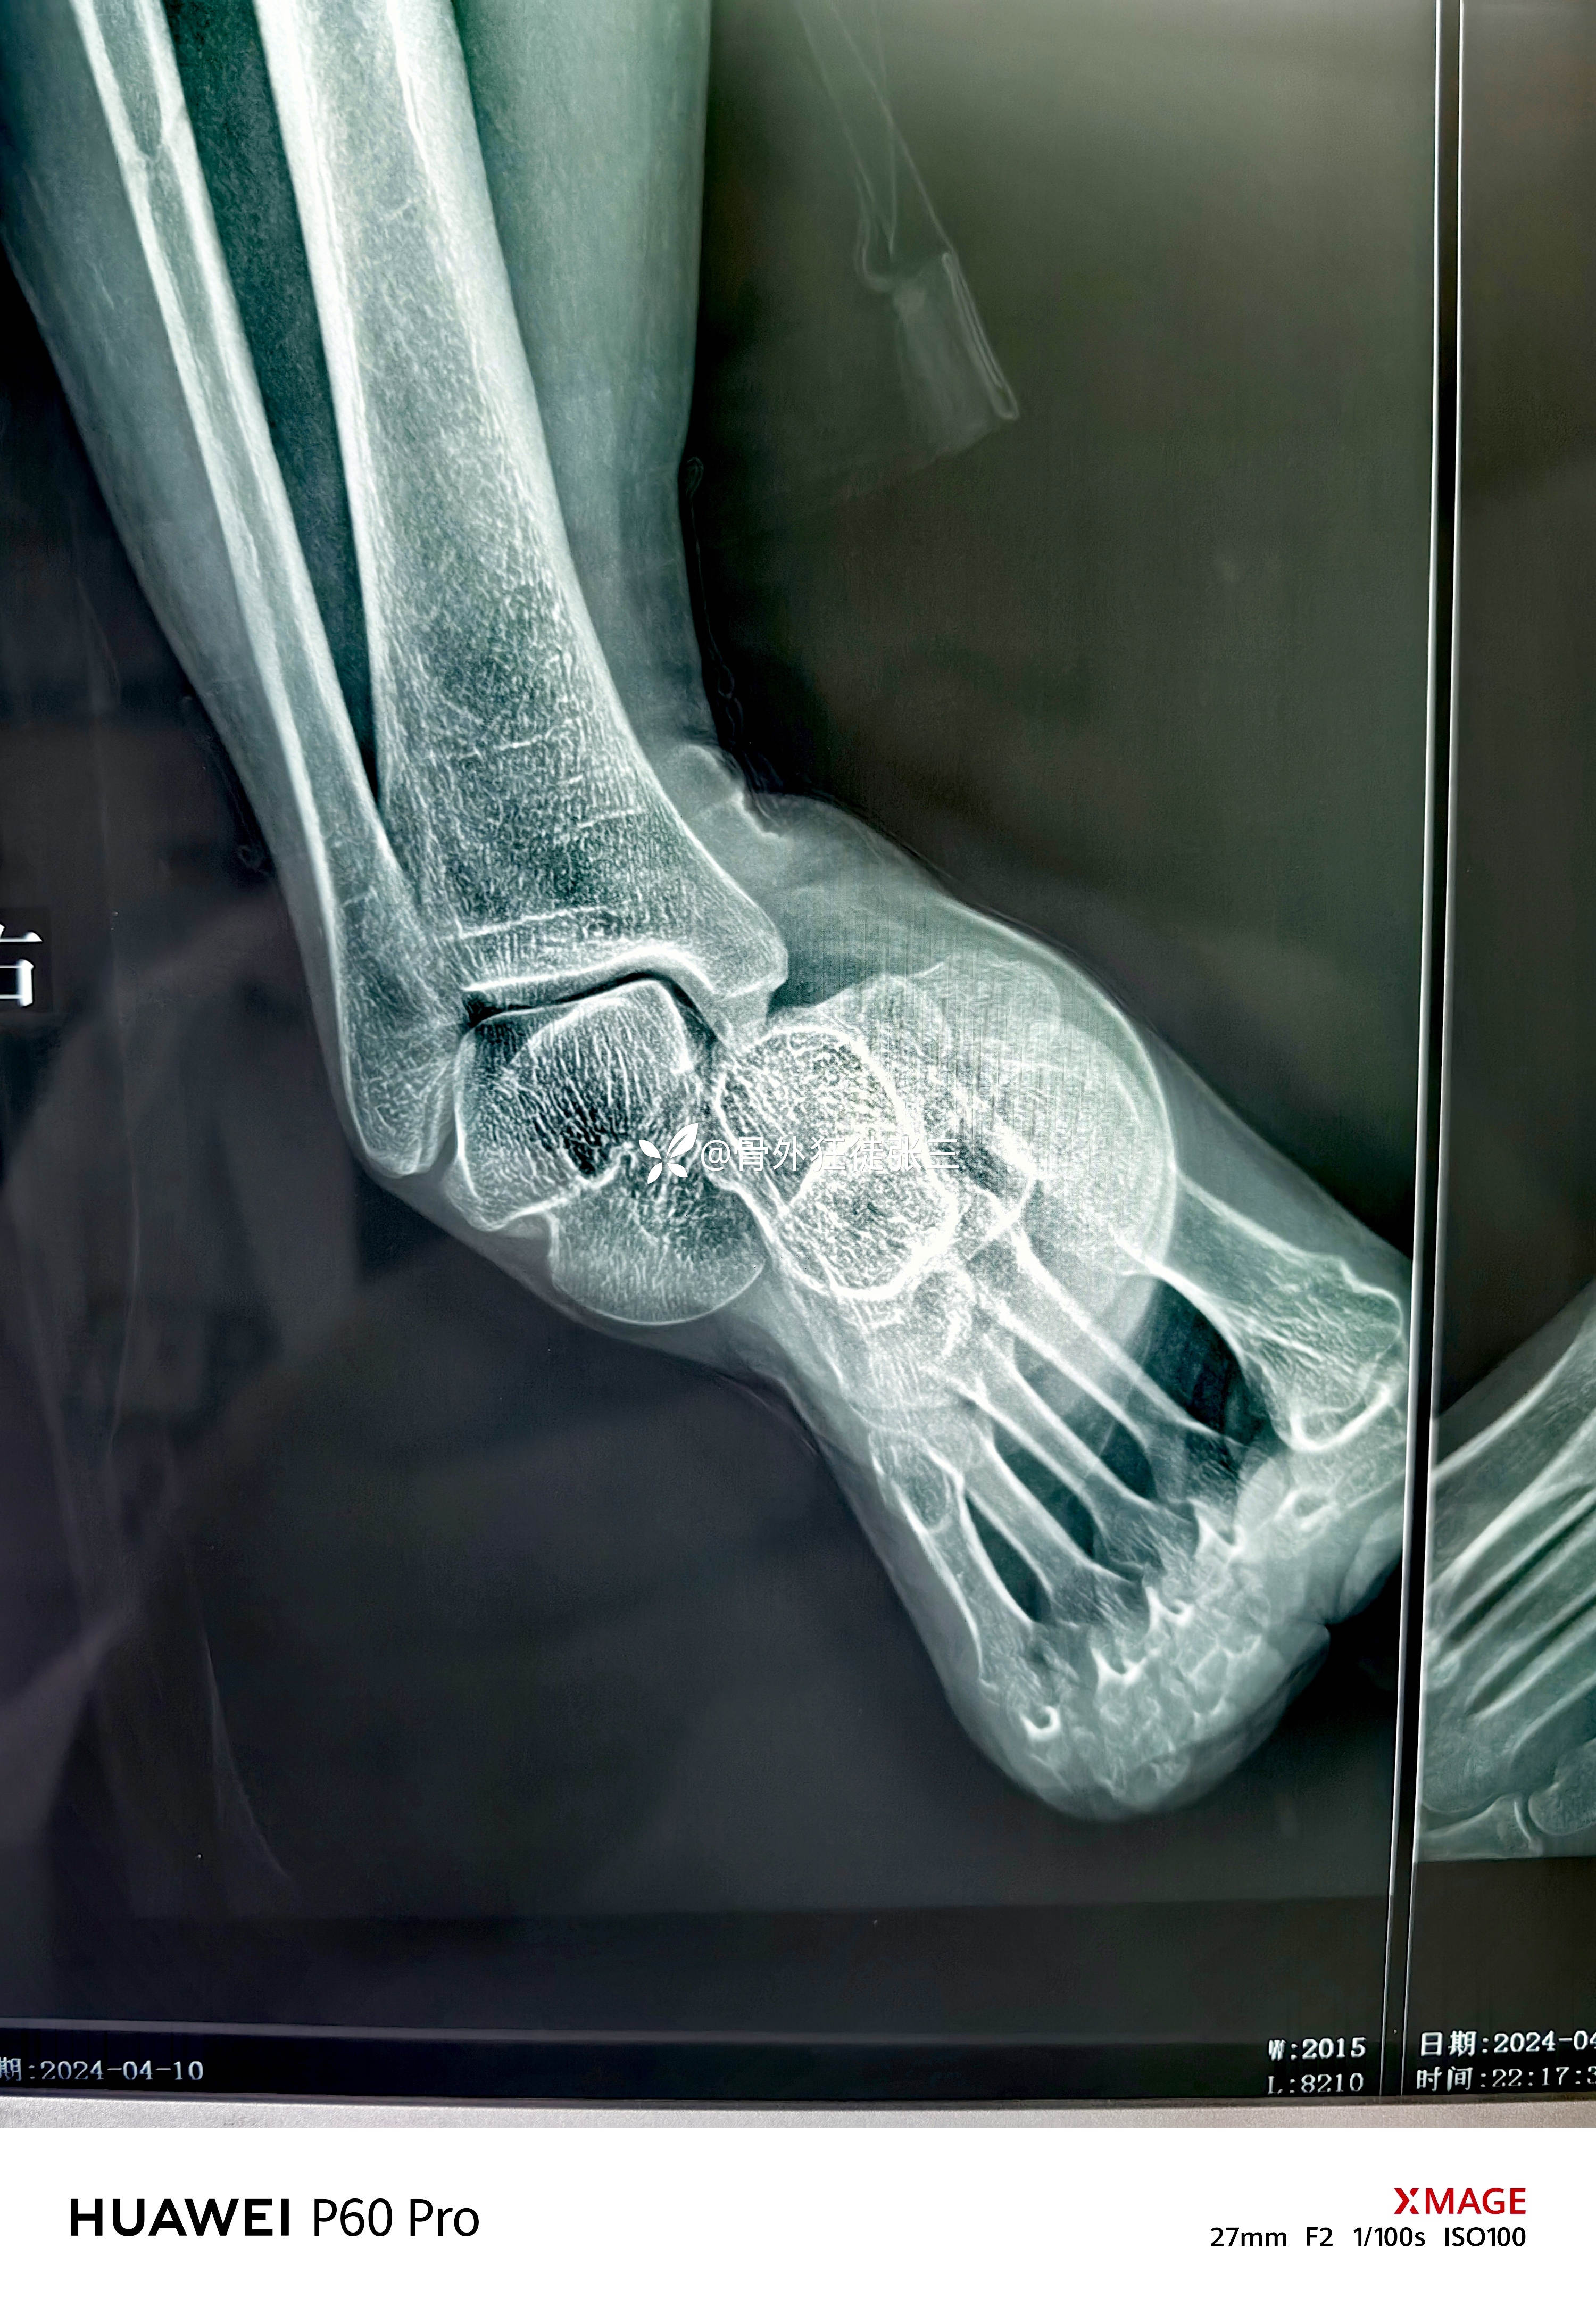

罕见损伤:距下关节脱位

主诉:车祸扭伤右踝关节致肿痛、畸形、活动受限1小时。

辅助检查:

右距下关节脱位(内侧型)